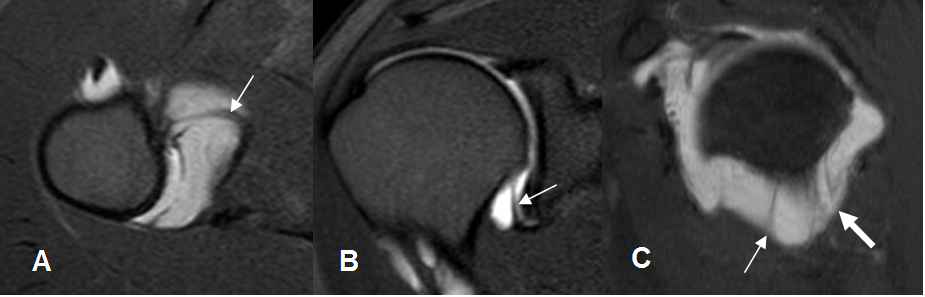

Fig 28. Labrum normal.

A: ArtroRM axial. Rebordes normales anterior y posterior.

B: ArtroRM coronal. Rebordes normales superior e inferior.

C: RM sagital en T2. Labrum adherido a la cavidad glenoidea.